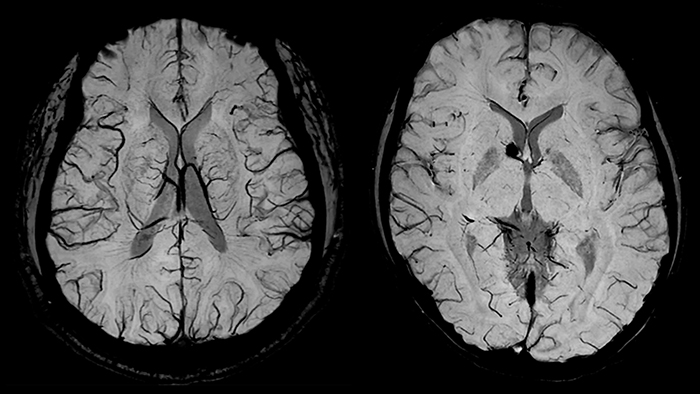

SWIp активно используется для визуализации точечных кровоизлияний в глубоком подкорковом белом веществе, которые сопровождают диффузные аксональные повреждения головного мозга. Клинический прогноз зависит от числа кровоизлияний, а недавнее исследование [11] выявило связь между кровоизлияниями в ряде глубоких подкорковых областей головного мозга и повышенной вероятностью нарушения исполнительных функций у подростков. Таким образом, остро стоит необходимость обнаружения и точной локализации церебральных микрокровоизлияний [12]. Эти точечные патологические изменения при диффузно-аксональном повреждении не столь заметны при использовании традиционных методик МРТ-визуализации (рис.8). Использование фазовой информации обуславливает более высокий контраст кровоизлияний на SWI изображениях, как следствие, даже чувствительные к неоднородностям поля T2* последовательности уступают SWI изображениям по чувствительности при диагностике диффузных аксональных повреждений [13].